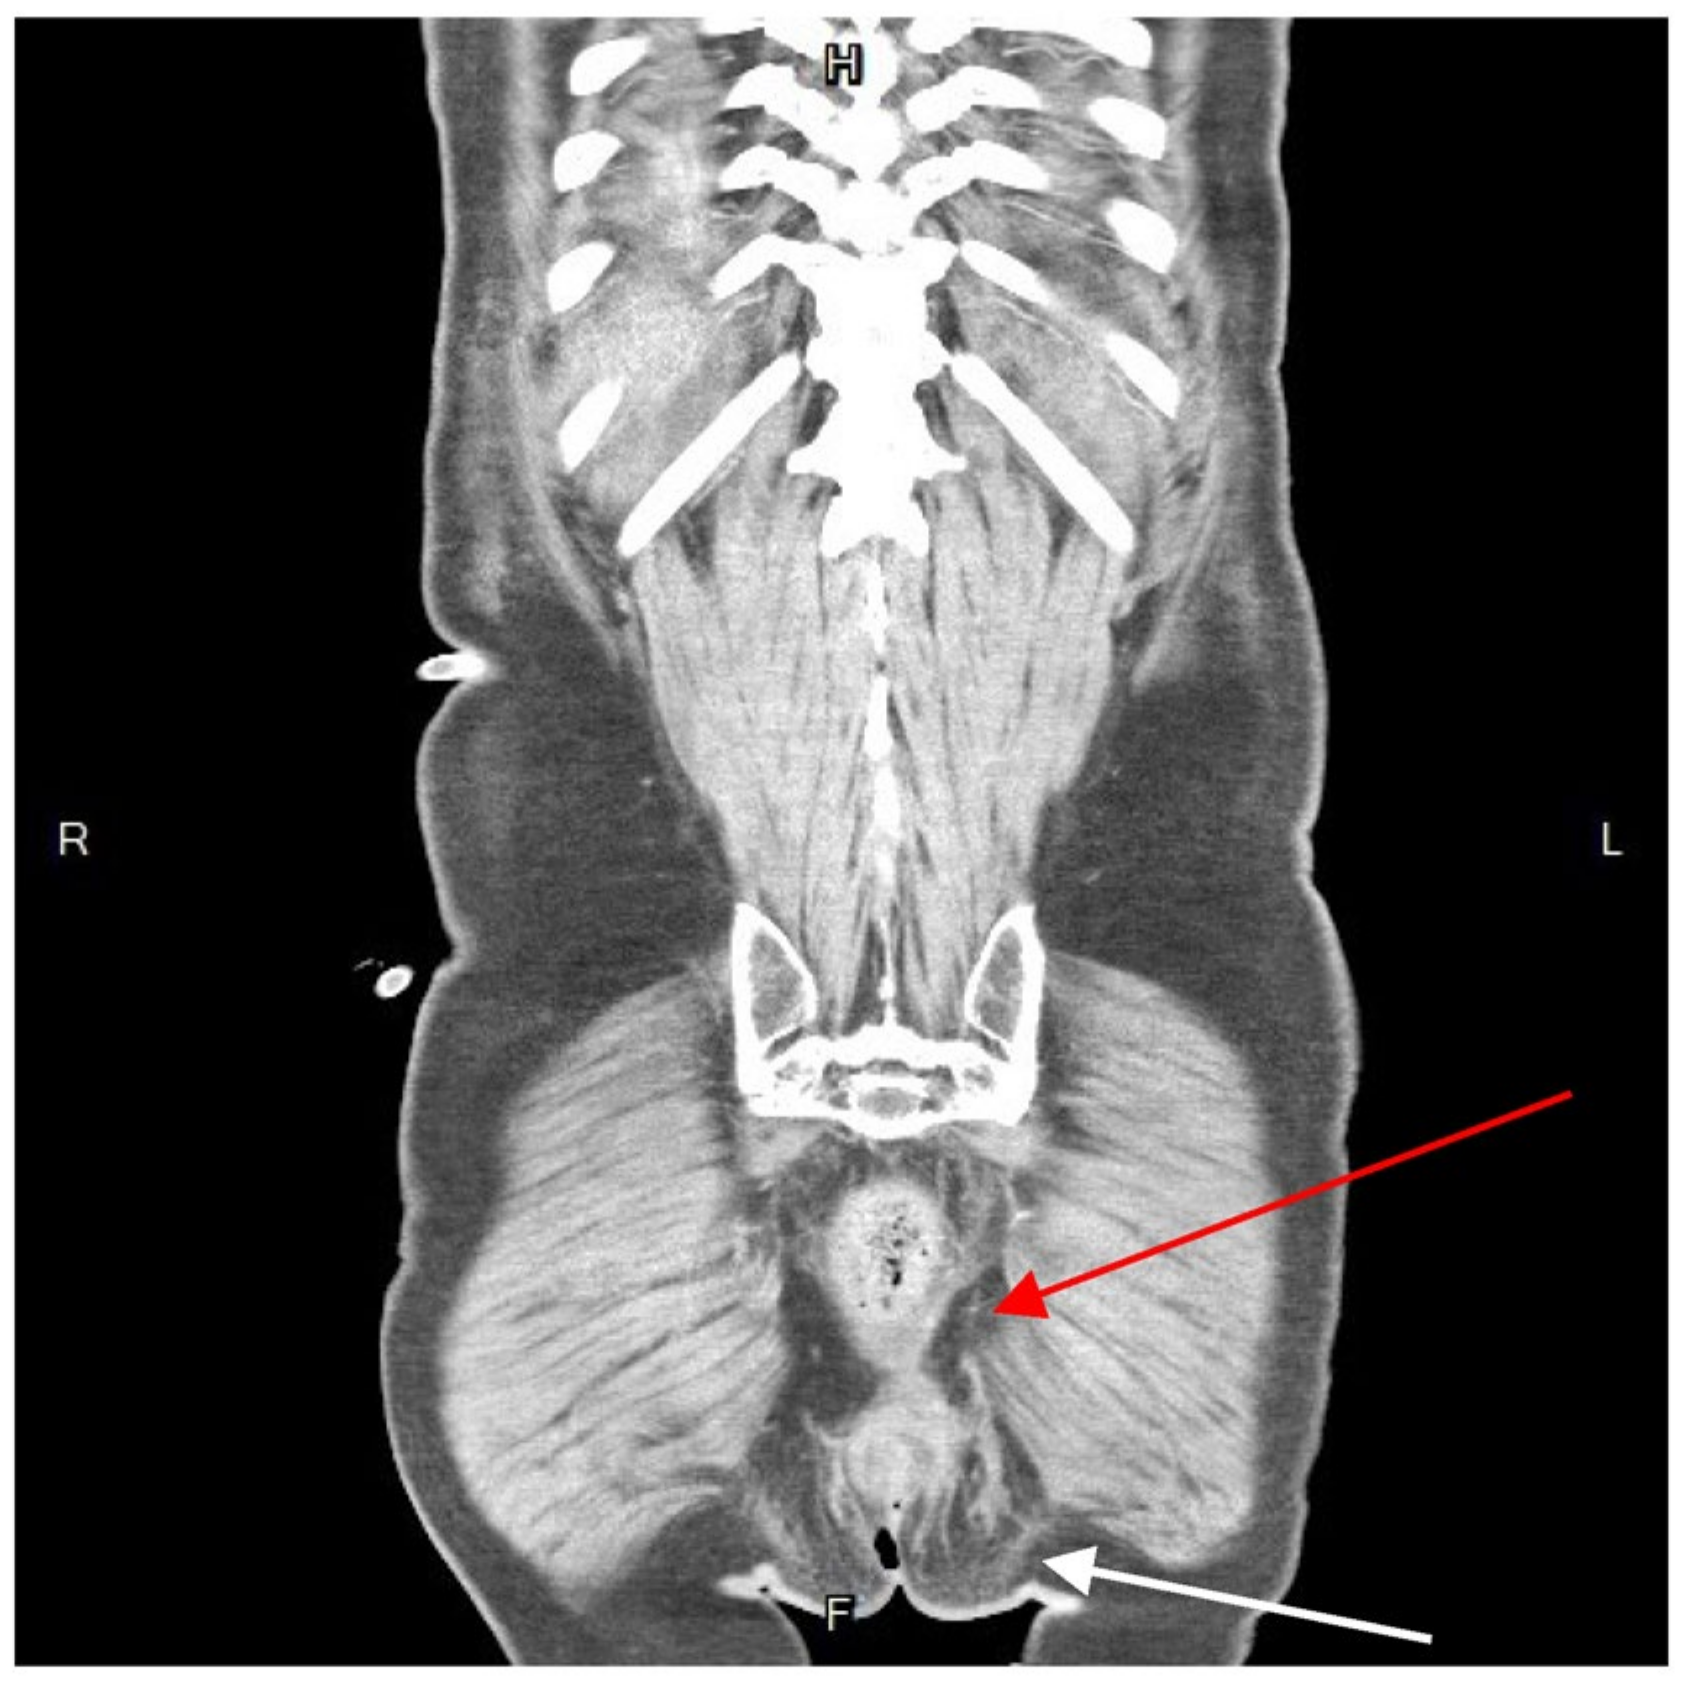

Further diagnostic measures included a plain abdominal radiograph, which showed no pneumoperitoneum or abnormal fluid accumulation. Laboratory findings consisted of an elevated white blood cell count and C-reactive protein level (white blood cells: 27,830/μL; neutrophils: 90.6%; C-reactive protein: 21.65 mg/L). Abdominal contrast-enhanced computed tomography (CT) showed a heterogenous fluid-filled perianal abscess measuring 5.0 × 4.4 × 6.8 cm (Figure 1) in the left perianal region, with extraperitoneal air spreading through the abdominal wall fascia (Figure 2 and Figure 3). The primary abscess was situated in the supra-levator space, potentially involving the levator muscle (infra-levator), as indicated by its migration from the perianal level to the extraperitoneal level. After a comprehensive review of the patient’s symptoms, medical history, age, and current status, immediate arrangements for endoscopic tests, including upper gastrointestinal endoscopy and colonoscopy, were not made. Additionally, gastrointestinal tract specimens, such as fecal samples for calprotectin and lactoferrin, were not collected, thereby not suggesting the likelihood of inflammatory bowel diseases.

Figure 1. Coronal view of contrast-enhanced computed tomography. A hypo-attenuated area (size: 5.0 × 4.4 × 6.8 cm) on the left side perianal, with spotted air and irregular contour (arrow). The abscess cavity showed contralateral extension to the supra-sphincteric direction (red arrow). R, right; L, left; H, superior; F, inferior.